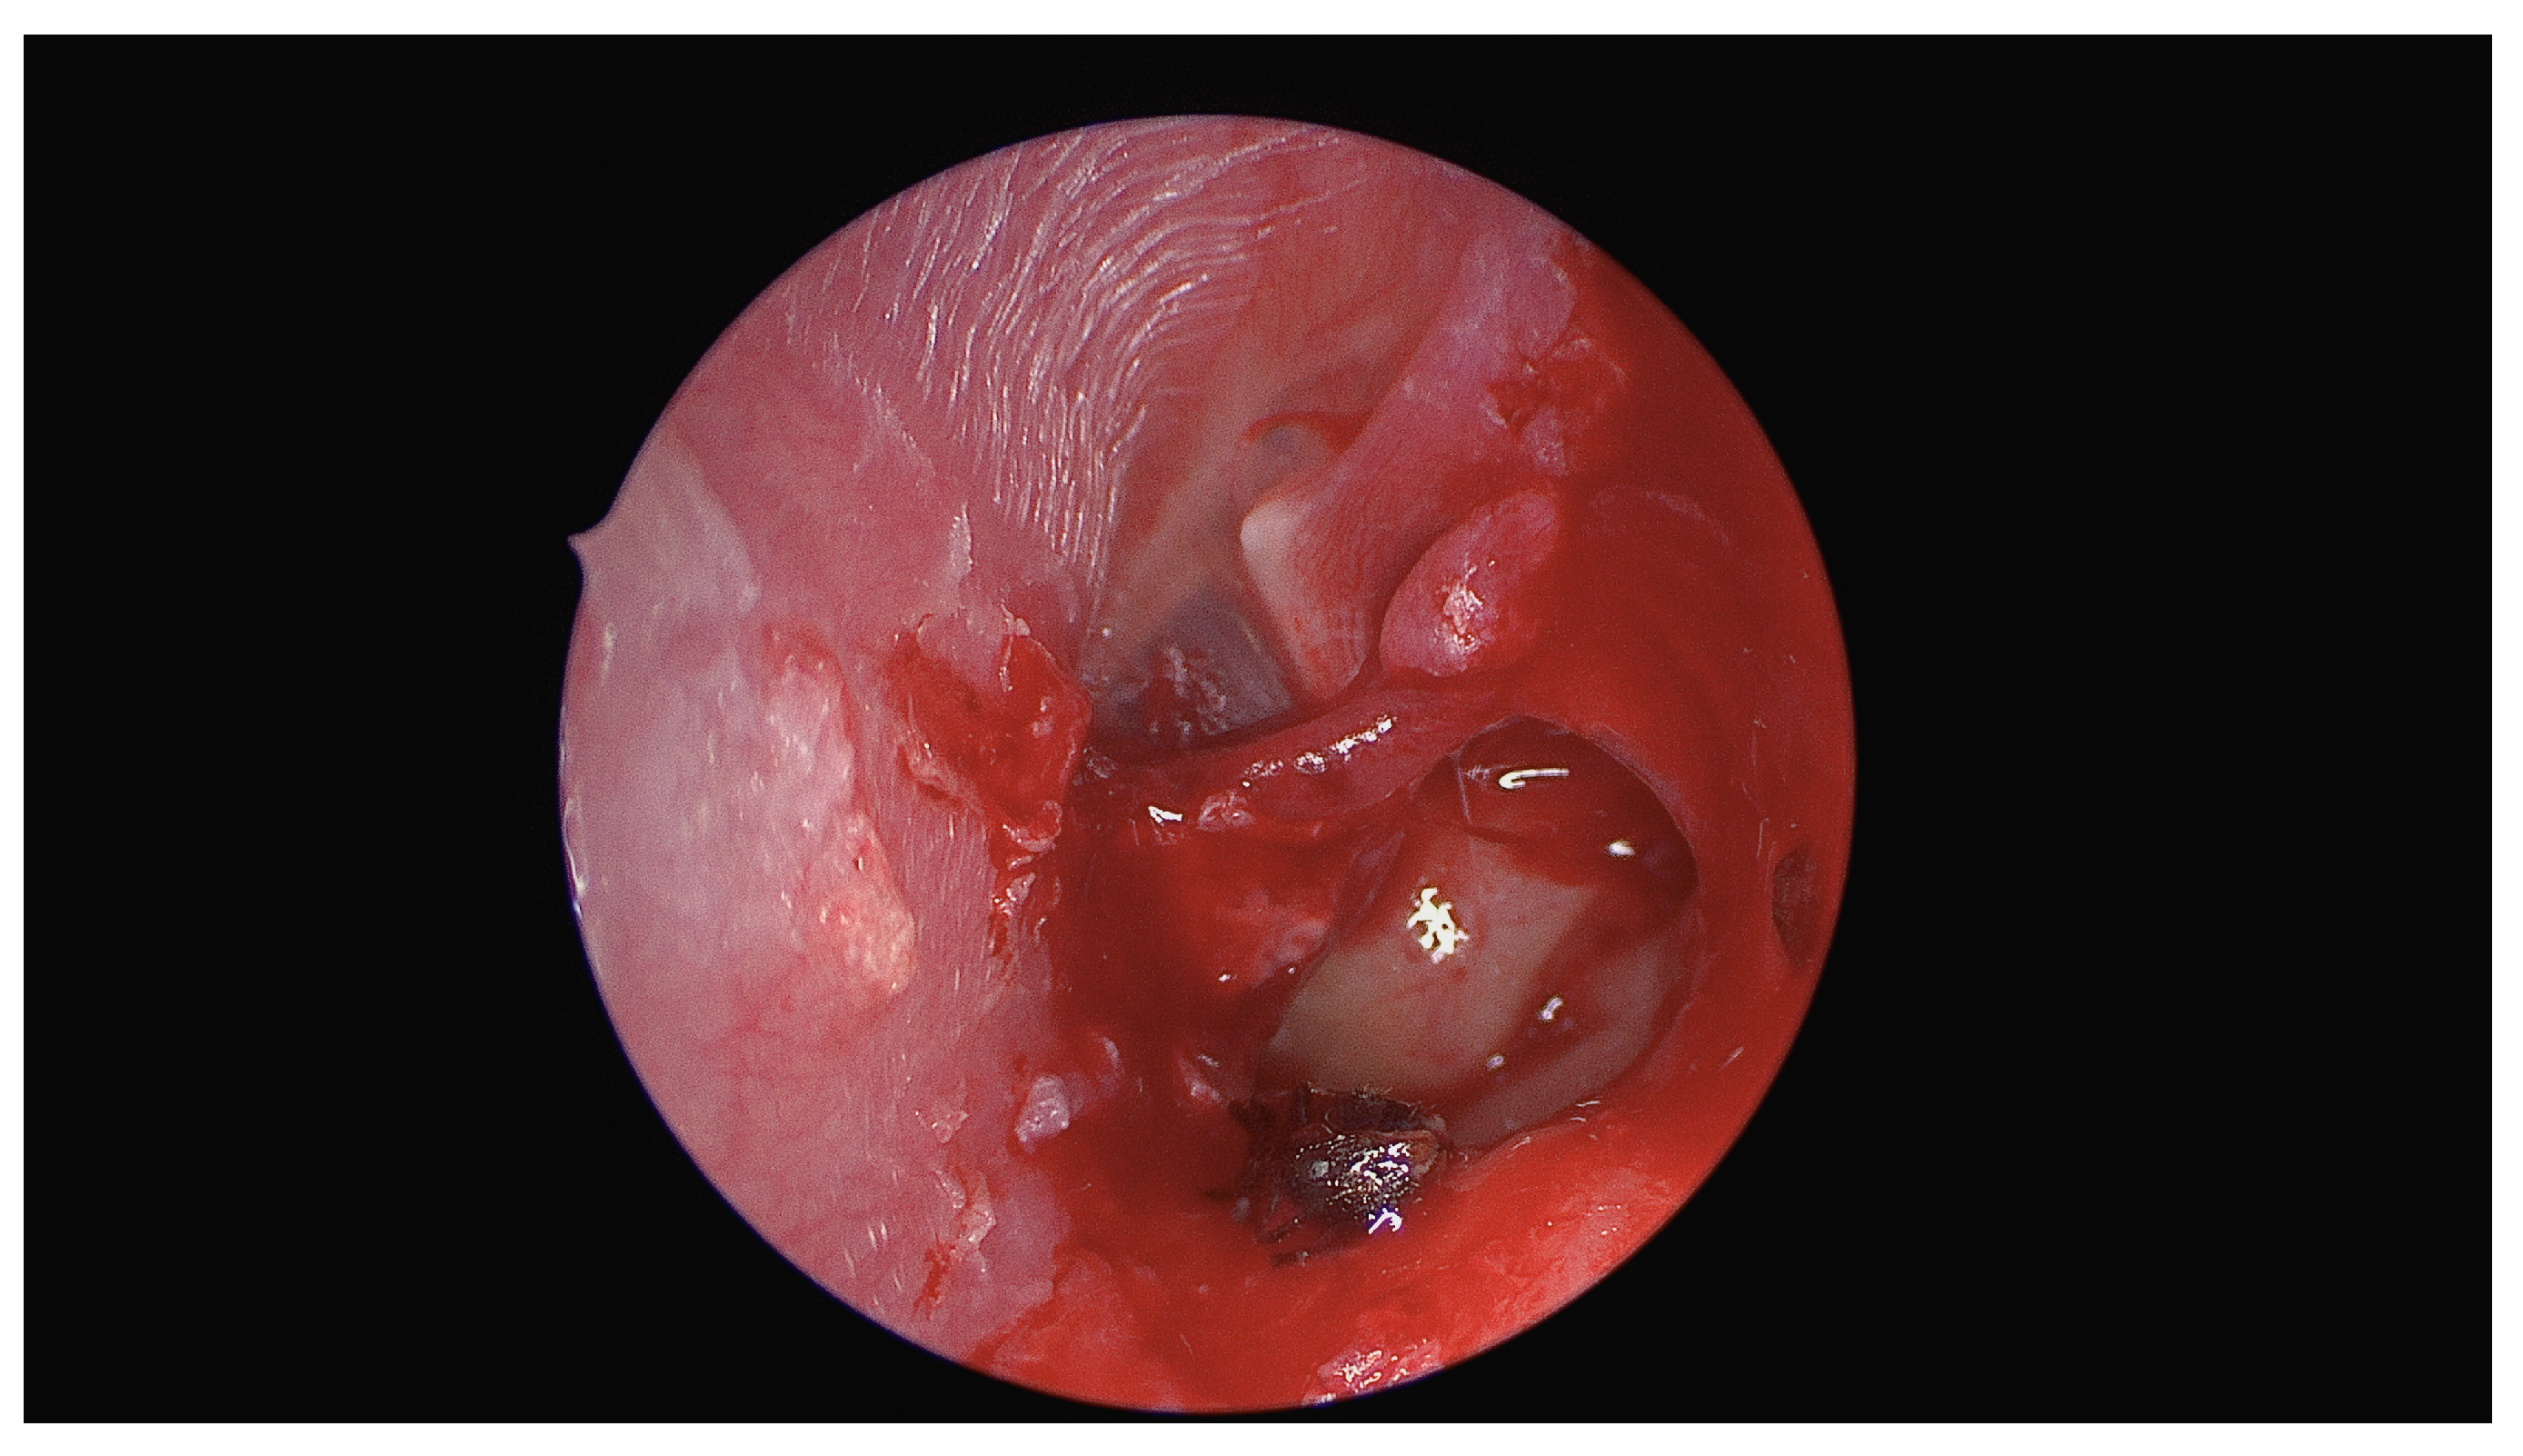

Unusual Foreign Body in the Middle Ear: Surgical Removal of a Live Ant Entering the Tympanic Cavity Through an Ear Drum Perforation